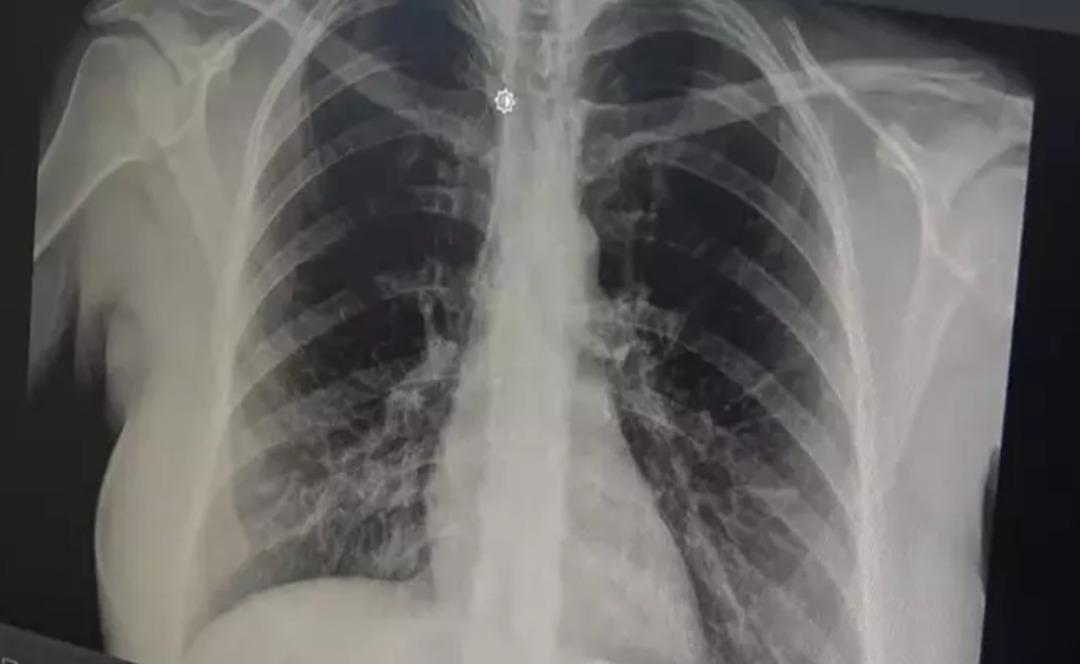

prof. Akut bronşitin solunum yolu virüslerinin neden olduğu bir hastalık olduğunu belirten Dr. Özlü, şöyle konuştu: “Günümüzde çok sık gördüğümüz bir hastalık. Genelde hastalar şöyle tarif ediyor: 'Öncelikle boğazım ağrıyordu, boğazım ağrıyordu. hafif ateş, burun akıntısı, hapşırma, geniz akıntısı ve öksürük: “2-3 gündür göğsümdeydi. Nefes alırken acı hissediyorum. İçeride bir çalı varmış gibi görünüyor. Nefes aldığımda göğsüm oraya sıkışıyor” çünkü aslında gerçek bu. “Bronşit, solunum yolu virüslerinin neden olduğu bulaşıcı bir hastalıktır. Bu enfeksiyon üst solunum yollarıyla sınırlı olmayıp alt solunum yolları ve bronşları da etkiliyor” dedi.

Akut bronşitin en önemli belirtisinin öksürük olduğunu vurgulayan Prof. Dr. Tevfik Özlü, “Kuru öksürük veya balgamlı öksürük şeklinde kendini gösterebiliyor. Bazen belirti daha çok hırıltılı solunum ve nefes darlığı şeklinde hissedilebiliyor. Yüksek ateş genellikle herhangi bir rahatsızlığa neden olmaz ancak bazen bakteriyel enfeksiyonlar da ortaya çıkabilir” dedi.

Bronşitin genel olarak hafif seyreden bir hastalık olduğunu ancak belirtilerin artması durumunda doktora başvurulması gerektiğini belirten Özlü, şöyle konuştu: “Altta yatan kronik bir hastalık, astım veya KOAH obstrüktif bronşit gibi bir akciğer hastalığı varsa, kronik hastalığın akut alevlenmesidir. buna hastalık eşlik edebilir ve genel akut bronşit, nefes darlığı, hırıltılı solunum, halsizlik, yorgunluk, yüksek ateş gibi ciddi semptomlarla ortaya çıkabilir veya Altta yatan kronik bir hastalık varsa ve semptomlarda alevlenme varsa doktora görünün, “Genelde hafif, tedavi edilebilir bir hastalık olduğunu söyleyebilirim” dedi.